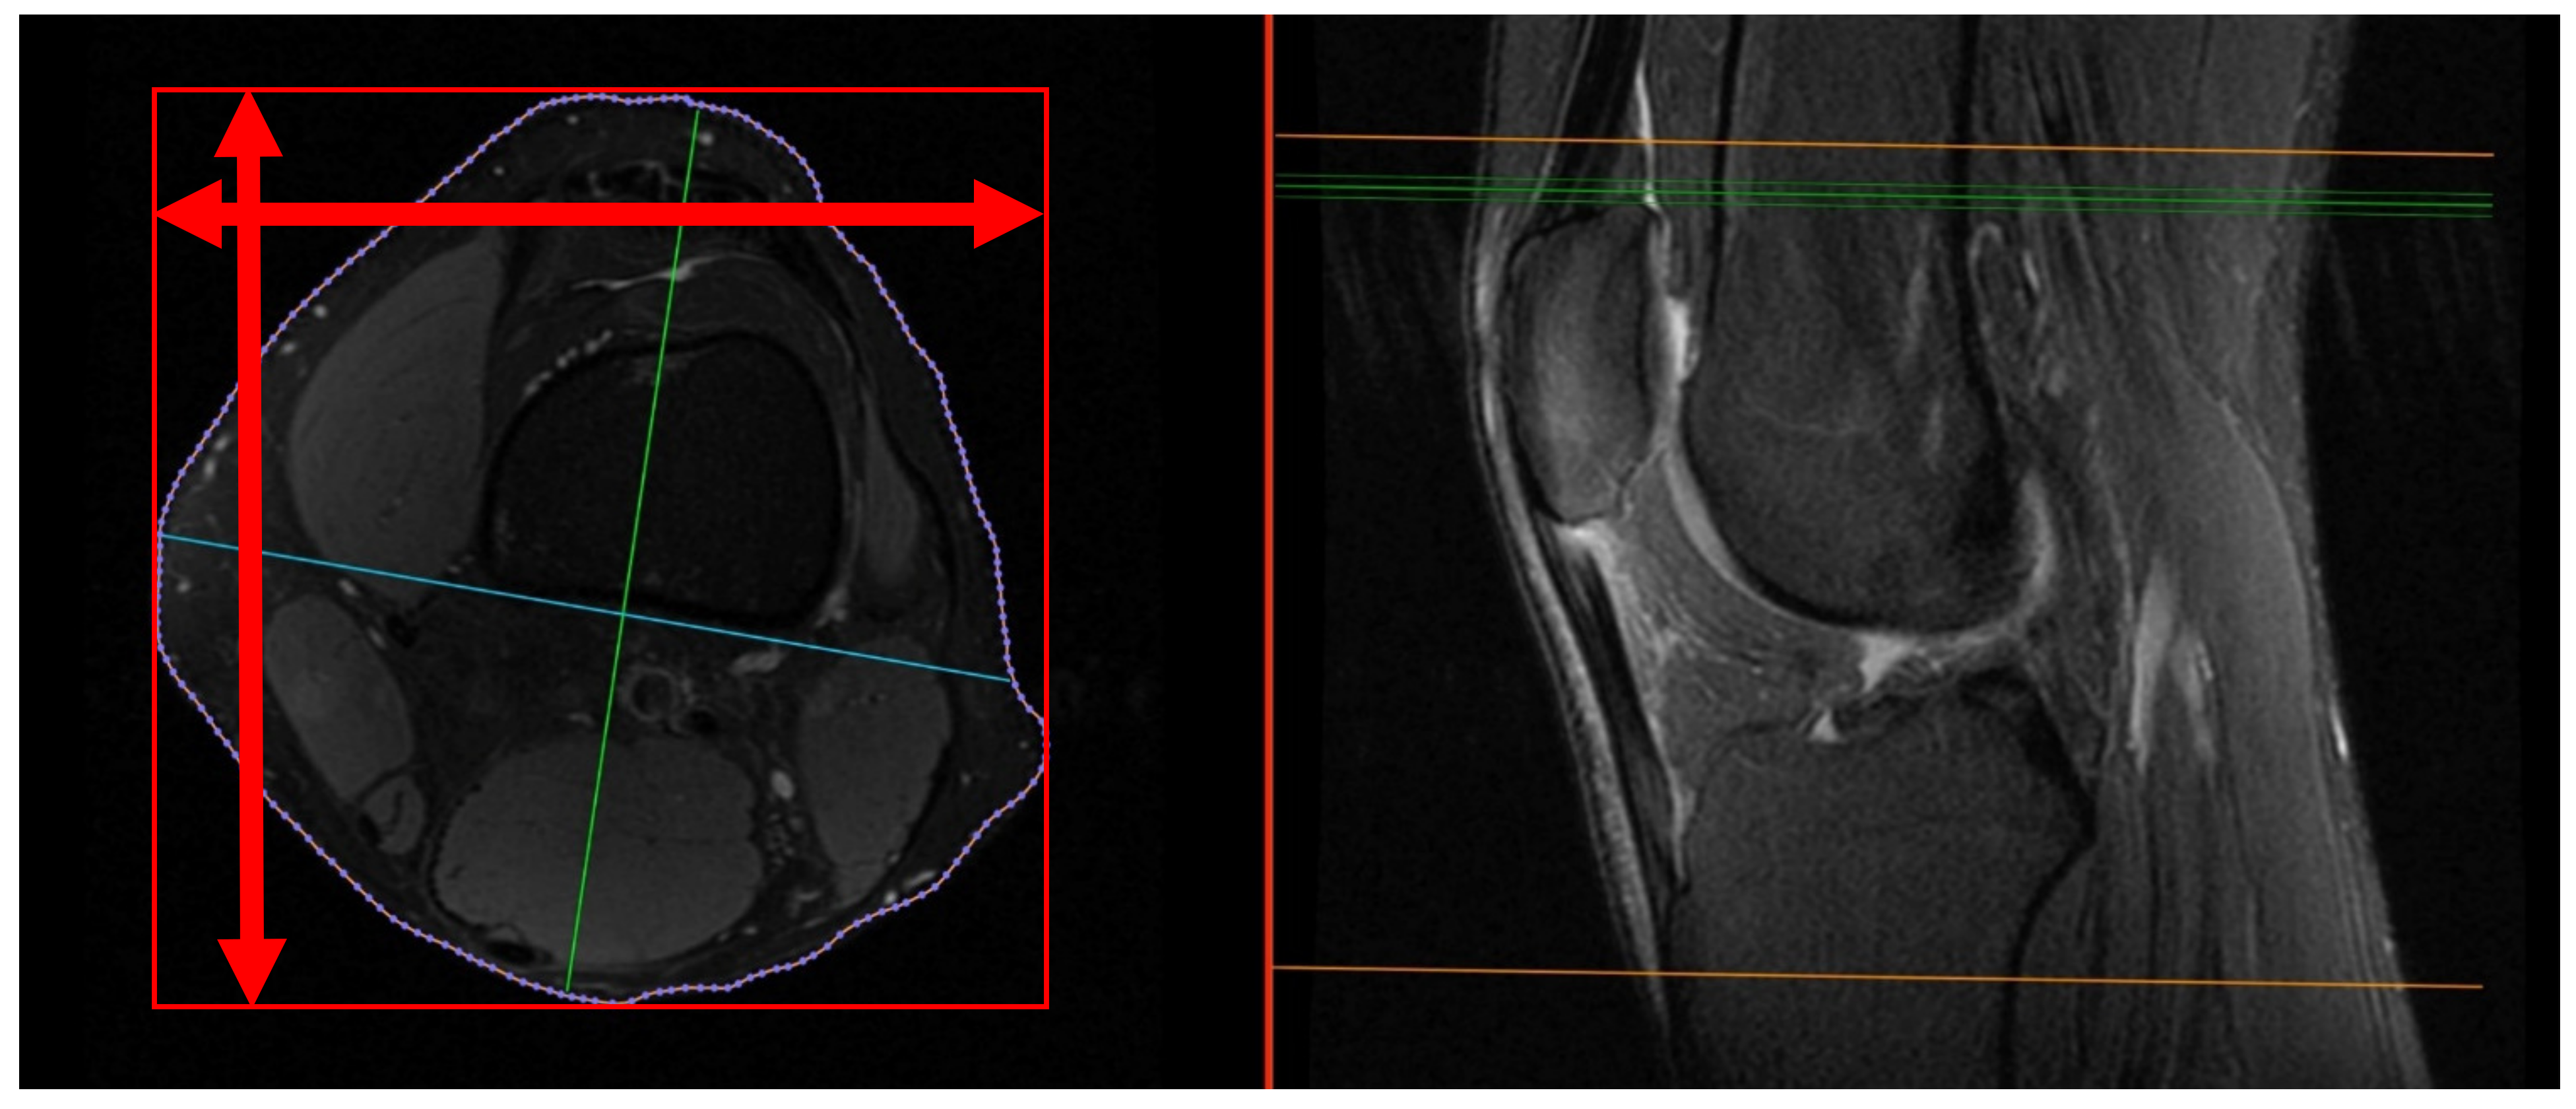

- Knee diameters were measured on axial PD-weighted images at the exact level of the patella upper pole (strictly antero-posterior = vertical, and medio-lateral = horizontal, independent of the leg position; Figure 2). The larger of these 2 diameters was taken as “maximal diameter”.

Figure 2. Knee diameters were measured on axial PD-weighted images at the exact level of the patella upper pole, indicated by the green line on the right image. Radiologists measured strictly antero-posterior = vertical and medio-lateral = horizontal (red arrows). The maximal diameter of the knee was not measured (green line on left image). - (3)

- The whole knee cross-sectional area at the same level was automatically calculated by the Osirix software (Figure 2),